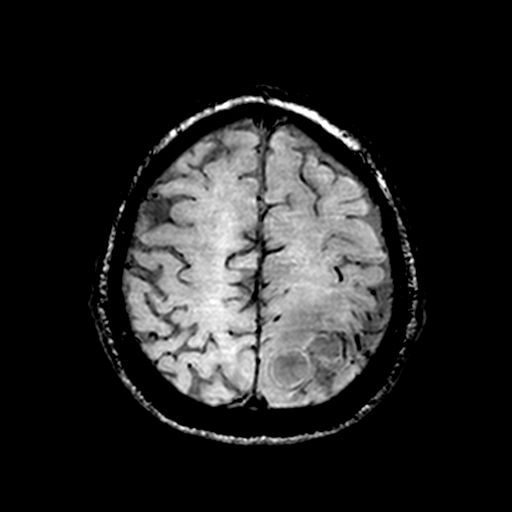

Caso neurorradiología

Paciente de 60 años con cuadro de 1 semana de evolución consistente en tropiezos frecuentes y alteración en la movilidad del miembro

inferior derecho. No refiere

cefalea u otros síntomas asociados, no pérdida de peso, no náuseas o emesis, no

sudoración nocturna. Antecedentes de hipertensión arterial y diabetes.

Resonancia magnética